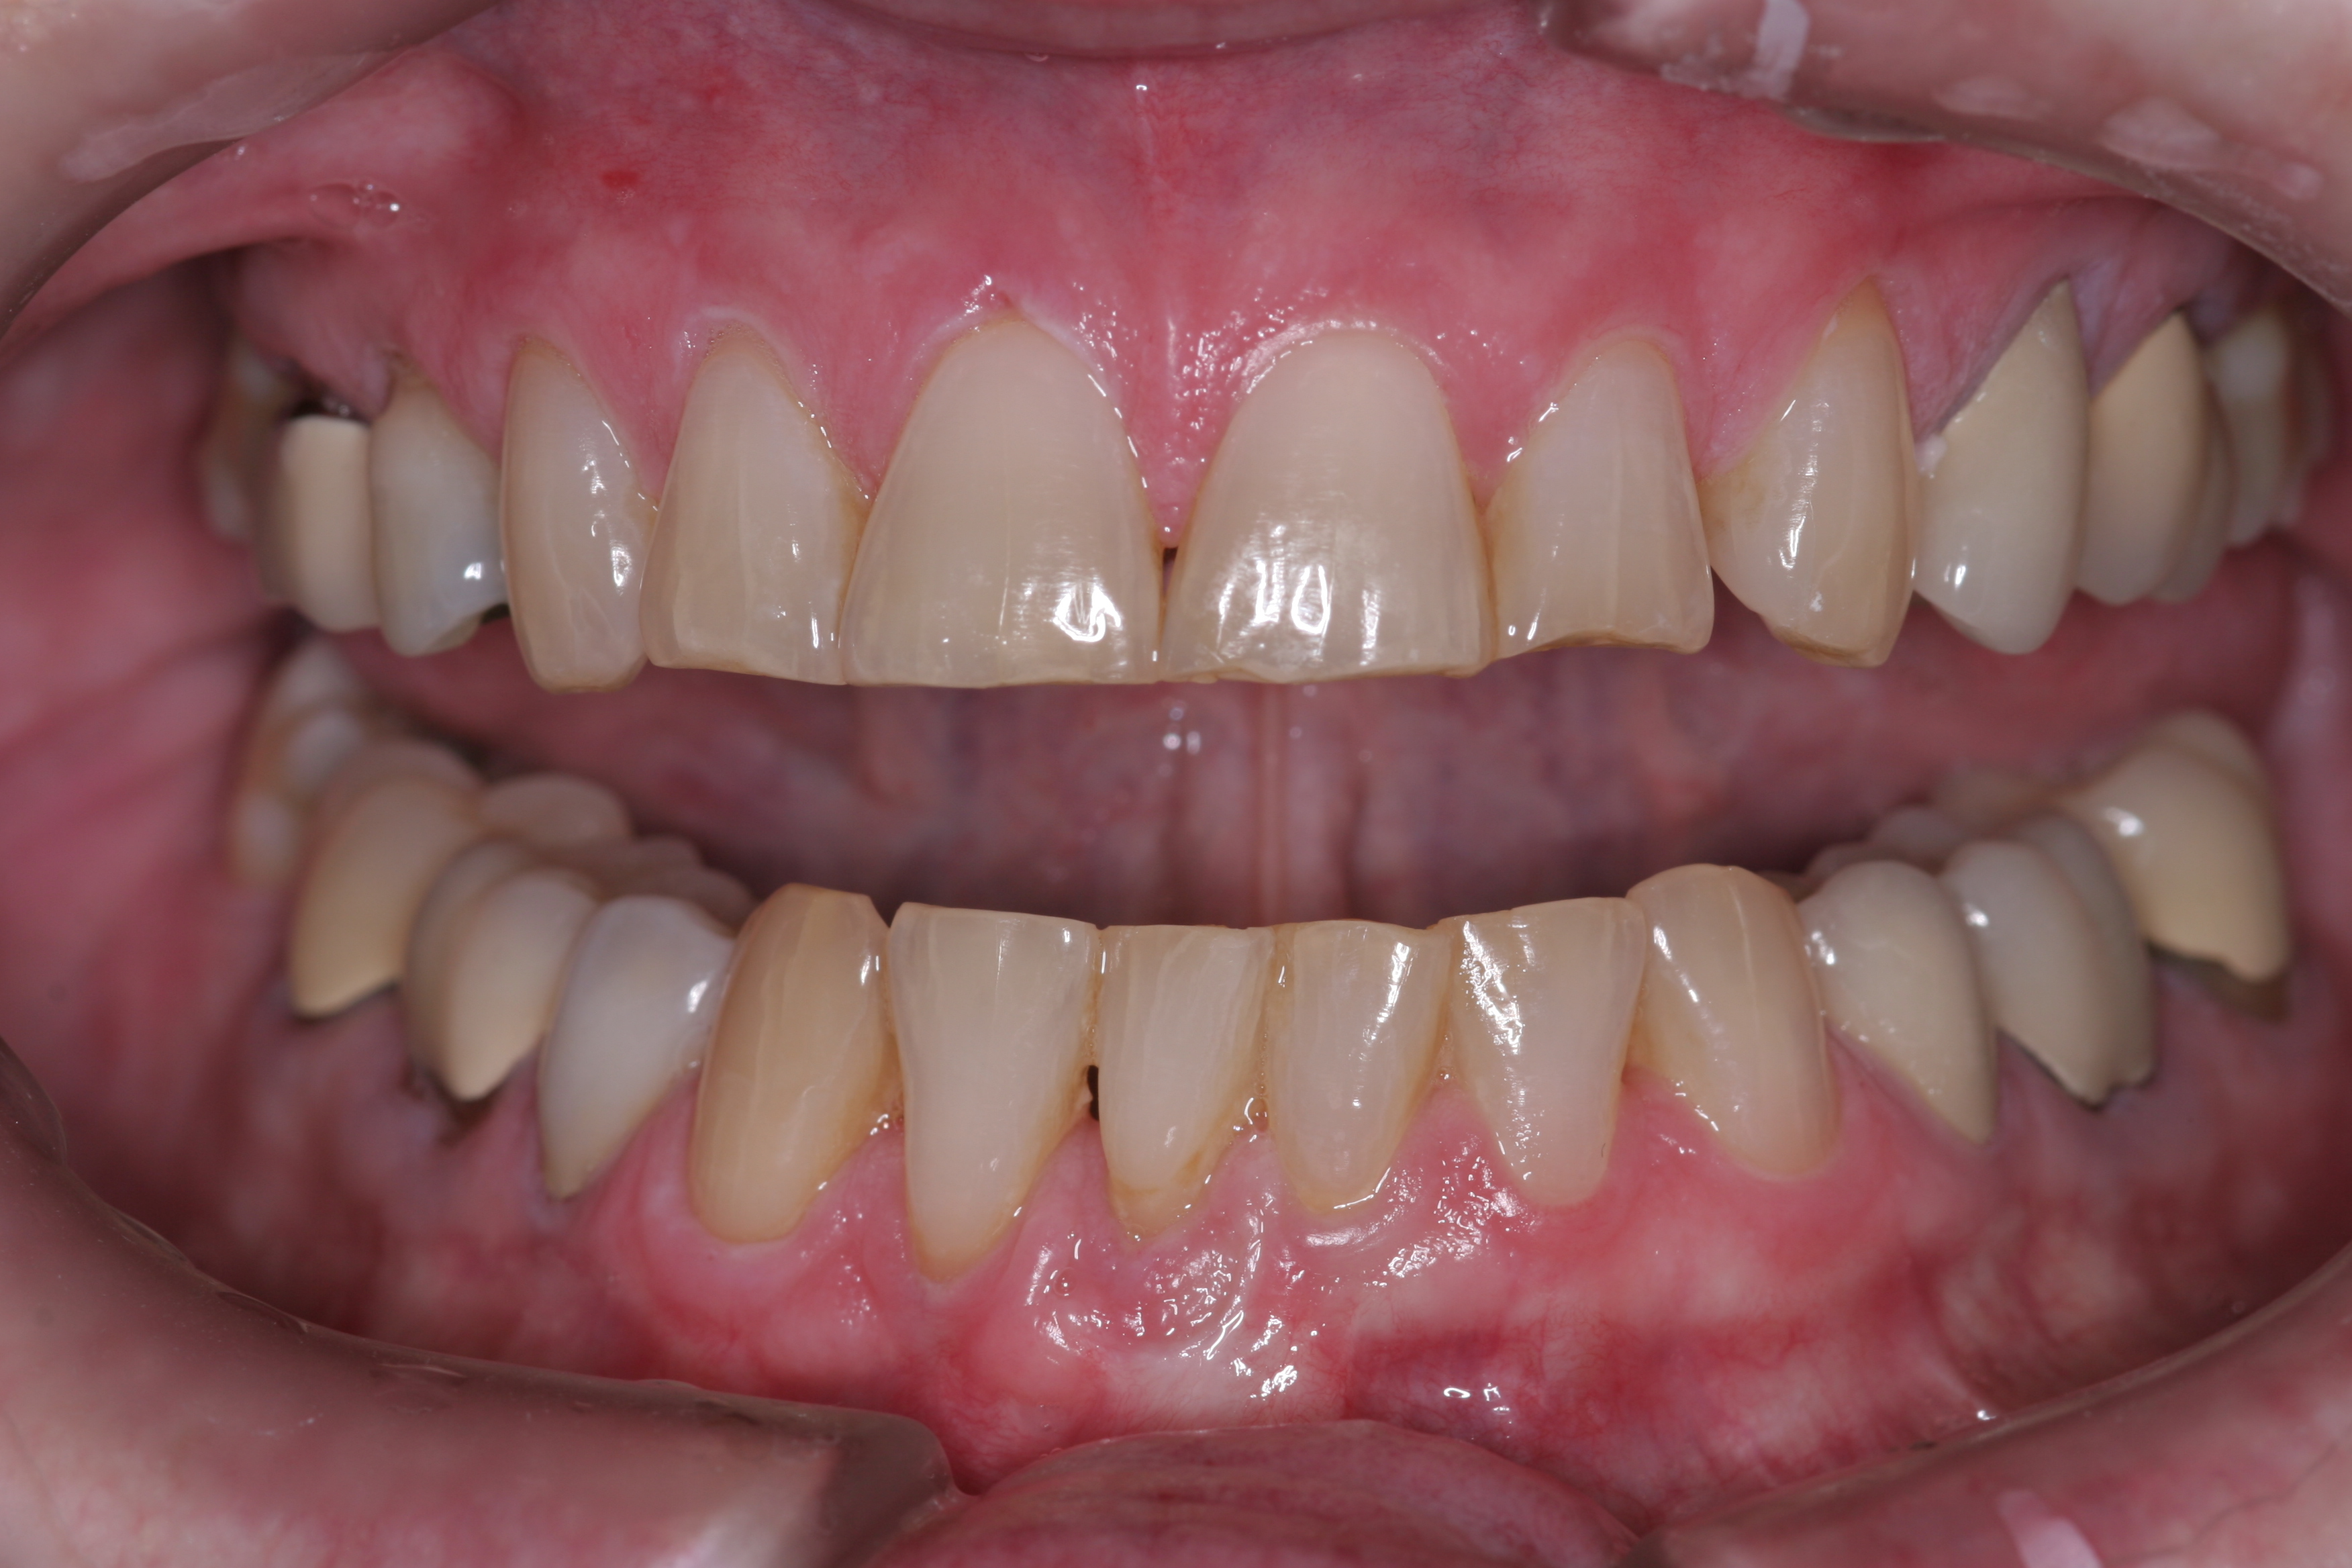

A patient presented with advanced generalized wear of her anterior teeth (Figure 10 and Figure 11). She was displeased with their overall appearance because of their color and wear (Figure 12). A complete examination was performed, revealing instability in her temporomandibular lateral poles bilaterally, sore muscles of mastication, advanced wear, a CR/MIP discrepancy, and loss of her anterior guidance due to the wear. Although the topic is beyond the scope of this article, the patient was also screened for possible sleep apnea. This included an evaluation of the Mallampati score, previous sleep therapy evaluation or treatment, snoring history, an evaluation of her neck size, her weight status, and the presence of the tonsils and their size. In every case, if this clinician suspects airway obstruction to be playing a role in tooth wear issues, the patient is referred to a sleep physician. The patient in this case displayed few apnea risk factors, and the patient’s anterior wear facets fit together like a “lock and key” pattern seen in parafunctional activity. Splint therapy was initiated to stabilize the joints and muscles. A repeatable CR position was verified through load testing. At this point diagnostic models, photographs, a CR bite record, and a facebow were taken and recorded.

(10.) A patient presented with advanced generalized wear of her anterior teeth, and was displeased with their overall appearance because of their color and wear.

Figure 10

(11.) A patient presented with advanced generalized wear of her anterior teeth, and was displeased with their overall appearance because of their color and wear.

Figure 11

(12.) A patient presented with advanced generalized wear of her anterior teeth, and was displeased with their overall appearance because of their color and wear.

Figure 12